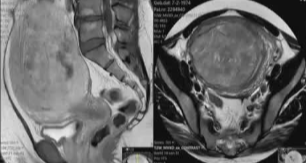

基于术前的磁共振成像特征以及血管造影信息

术前 |

术后 |

双侧子宫动脉栓塞,右侧1安瓶 500-700μ吗,左侧4安瓶500-700μm +7安瓶 700-900μm 可吸收微球 |